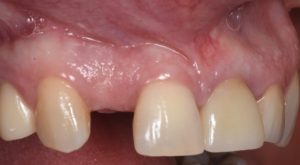

This video demonstrates implant placement in the esthetic zone combined with simultaneous guided bone regeneration (GBR). The case focuses on surgical decision-making, specifically how to determine when a staged approach is indicated versus when simultaneous implant placement and GBR can be predictably performed.

The procedure is presented step by step, including flap design and management, defect assessment, membrane selection and stabilization, flap advancement, and suturing techniques. Emphasis is placed on achieving tension-free closure and maintaining hard and soft tissue contours critical for esthetic success.